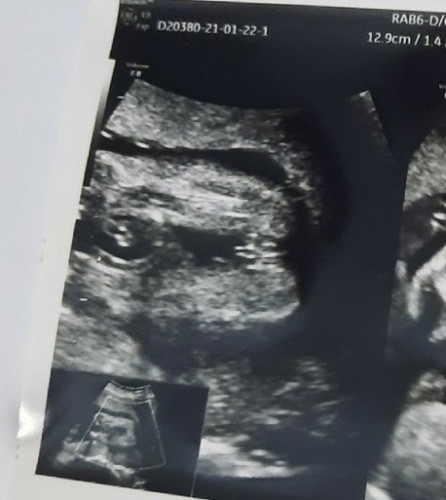

แม่ๆว่าเป็นผู้100%ไหมคะ

อยากขอความมั่นใจแต่หมอบอกว่าผู้หญิง กลัวตอนคลอดแล้วคดีพลิก😅

อาจหนีบไว้ค่ะ ถ้าบอกผู้หญิงมีโอกาสหนีบไว้ค่ะ แต่ถ้าผชจะเห็นชัดค่ะ(ถ้าเค้าไม่หนีบนะคะ)

เหมือนหญิงนะค่ะ เหนเปนกลีบๆ